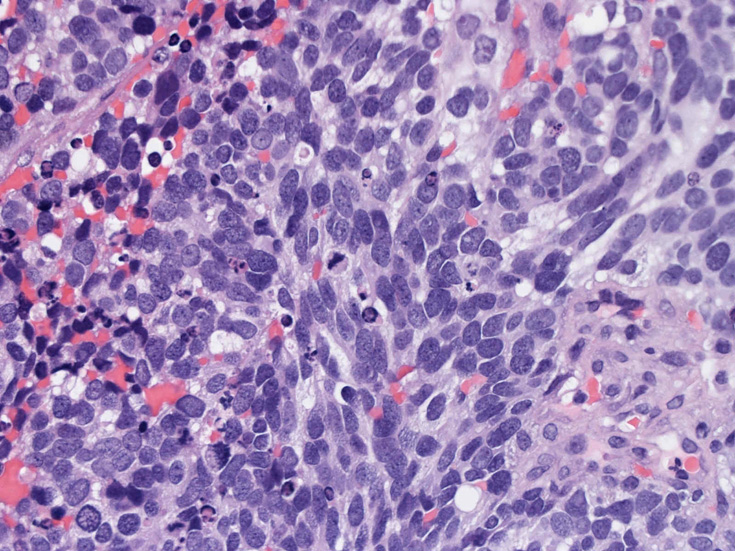

30歳代男性 鼻腔腫瘤の生検組織

厳密にはalveolar patternが明らかではなく, solid typeに入る症例かもしれない。異型細胞増殖胞巣が線維化組織に取り囲まれるように散在している. 小さな生検組織のため全体像が不明である。